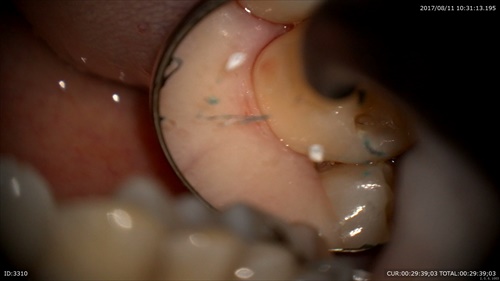

あれっこれはなんだ?歯と歯の間に歯石?

ネギ!!

歯茎の溝(歯周ポケット)が深くなるとこのような物も自分の歯ブラシではとれなくなります。歯周病って怖いですね。